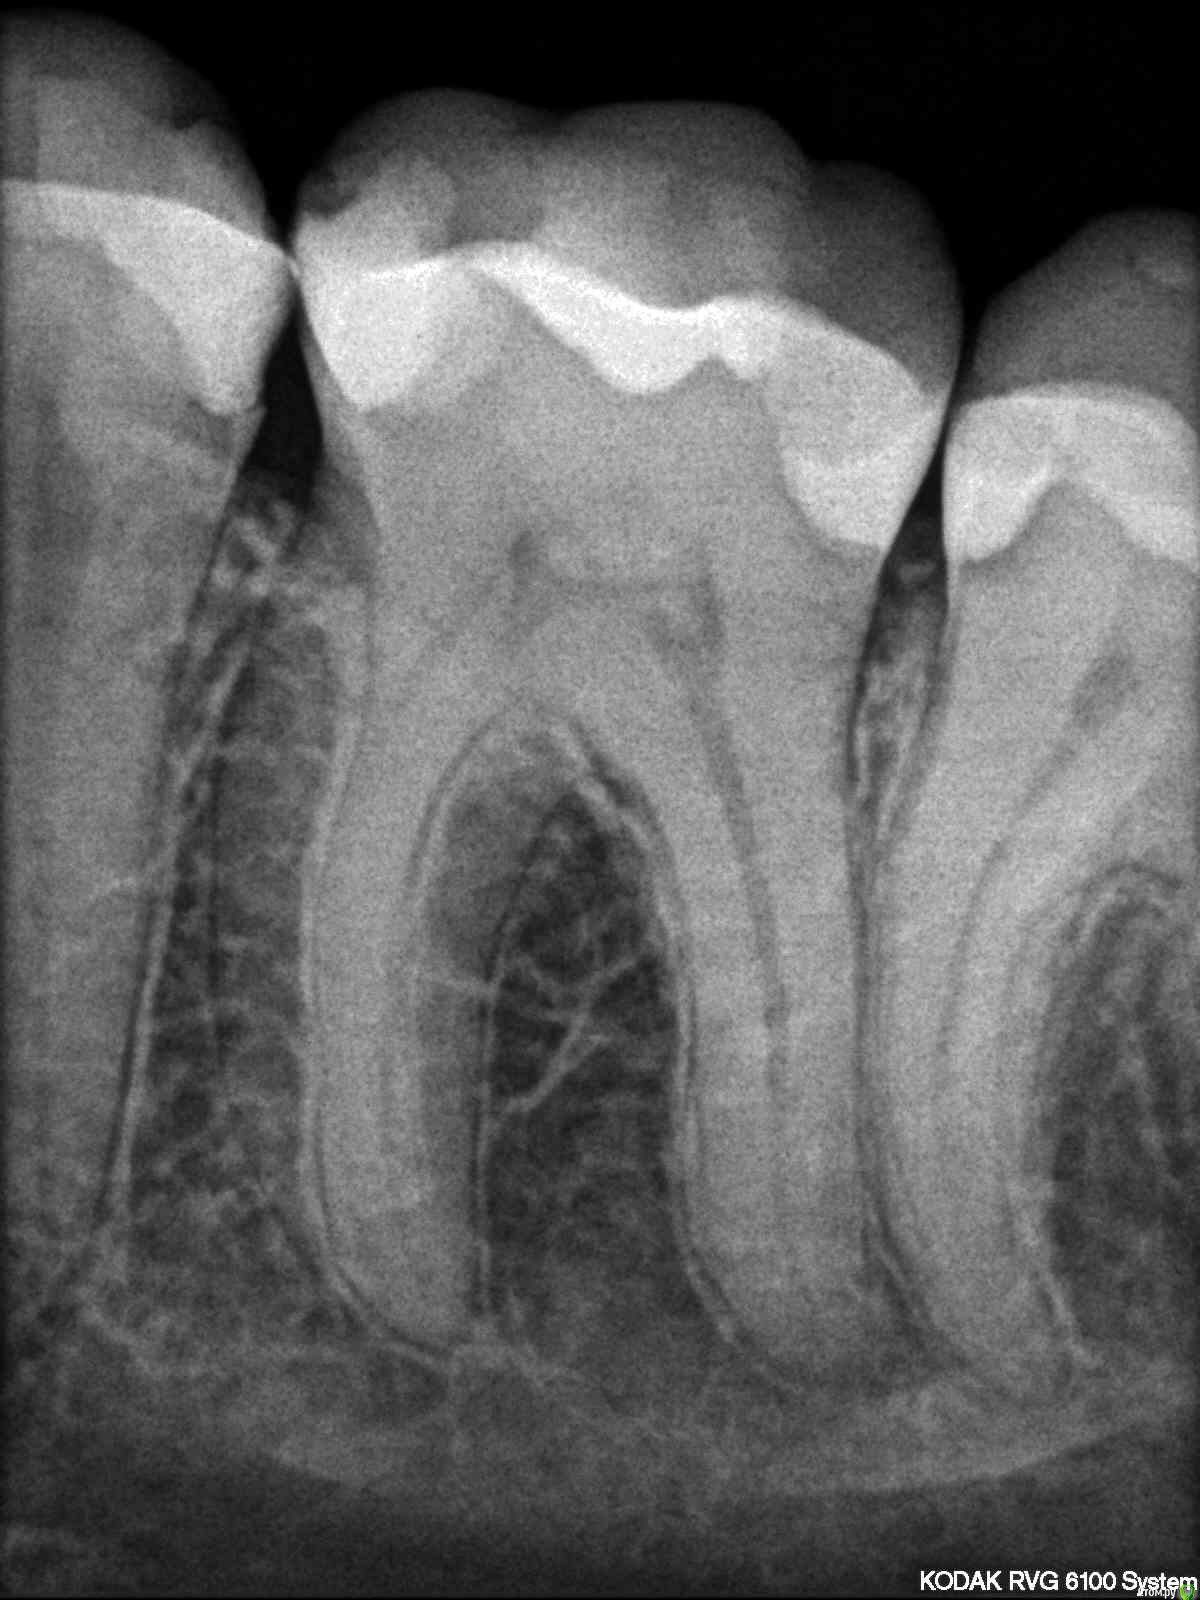

iamme Опубликовано 3 мая, 2017 Поделиться Опубликовано 3 мая, 2017 Все началось с того, что попал орех между 35, 36, увеличилось расстояние и стала застревать пища. В 35 зубе уже переделывали пломбу года 4 назад, чтобы восстановить контактный пункт, и вот опять. Стоит ли оставить все как есть или надо лечить? Я сходила просто на профилактический осмотр в свою клинику, врачу показалось, что с контактным пунктом более менее ок. Снимок не делали. Сказали лечить средний кариес на верхнем клыке (там вообще нет пломбы). Тогда сходила в другую, врач сделал снимок, сказал, что в 6 возможно пульпит, а в 5 кариес - надо лечить сначала 6. А клык менее важен (со средним кариесом согласился) В третьей сказали, что наоборот: в 6 кариес, а в 5 пульпит. Сначала 5. Надо сказать, лечить я лишний раз боюсь, так как уже напрасно пролечила один зуб. Вопрос к вам, надо ли что-то лечить, и что в первую очередь? Прикладываю снимок 35,36 Ссылка на комментарий

Pan Опубликовано 3 мая, 2017 Поделиться Опубликовано 3 мая, 2017 (изменено) порой удивляет осведомленность в терминах некоторых пациентов похвальнос. В 36 желательно переделать контактный пункт с восстановлением анатомического образования - межбугоркового валика в месте контакта с 35. Пломба в 35 также требует замены. Что бы подтвердить диагноз пульпита, данных не достаточно, нужны сбор анамнеза и дополнительные методы обследования. Изменено 3 мая, 2017 пользователем Pan 1 Ссылка на комментарий

St. Опубликовано 3 мая, 2017 Поделиться Опубликовано 3 мая, 2017 Нет, вы не совсем правильно поняли. Контакт это 2 зуба - в Вашем случае 5 и 6, чтобы не застревала еда на обоих контактирующих зубах должны быть правильные выпуклые поверхности, без острых нависающих краев. На 6 пломба есть и форма правильная. На 5 пломба со сколом и кариесом. Поэтому и застреет.Если 5 оставить как есть , то кариес на нем пойдет глубже.и если сейчас вероятность лечить\не лечить канал грубо говоря 50/50, то потом точно придется лечить каналы. Вы сами стали бы себе лишний раз зуб (5-ку) пилить в данной ситуации? Я сама себе зубы не пилю, у меня есть доктор , которому я доверяю. А вообще зубы Ваши, соответственно решение принимать Вам 1 Ссылка на комментарий